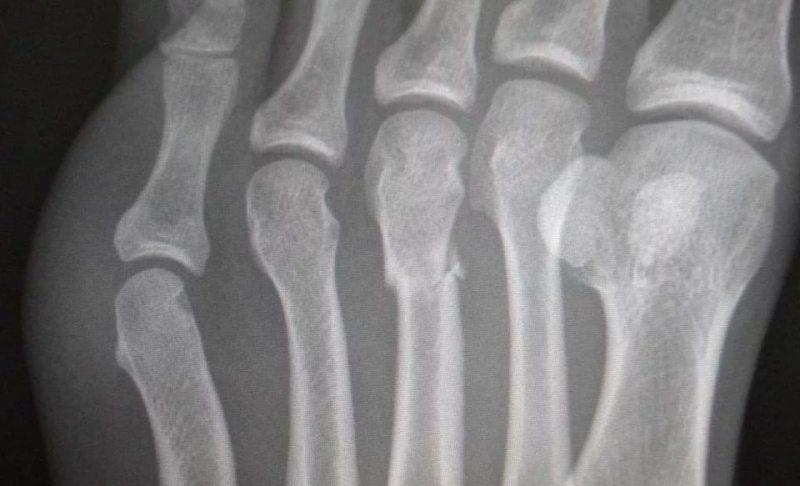

Перелом плюсневой кости обычно происходит из-за падения тяжелого предмета на стопу или ее защемления. При таком повреждении различают переломы головки, шейки или тела кости. Особенно часто встречается перелом Джонса (травма пятой плюсневой кости), который возникает при повороте стопы наружу.

На фото ниже вы можете увидеть перелом костей стопы:

- проведение рентгенографического исследования в двух проекциях;

- тщательное изучение повреждений с использованием МРТ или КТ (в случаях с серьезными травмами).